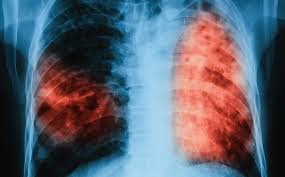

Туберкулоза

Опака болест